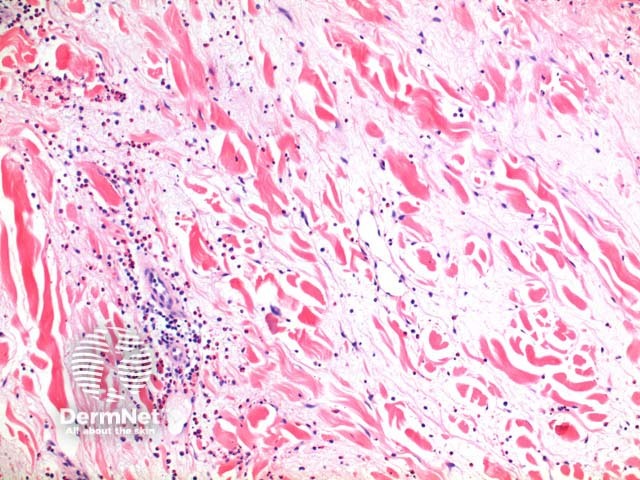

Scanning power view of Wells syndrome reveals a superficial and deep perivascular and interstitial inflammatory pattern (Figures 1 and 2). This can be seen to extend into the subcutaneous tissue (Figure 3) or even the underlying muscle. The inflammatory infiltrate is comprised of lymphocytes, histiocytes and abundant eosinophils (Figures 4,5 and 6). Degranulation of the eosinophils is seen forming flame figures (Figures 4 and 5). In this particular case extensive interstitial mucin is seen (Figures 4 and 5).

Bullous Wells disease: A subepidermal blister can form in the presence of prominent papillary dermal oedema.

Insect bite reaction: Typically here the infiltrate is more localised forming a wedge-shaped pattern possibly with focal overlying epidermal changes. In some cases discrimination is not possible and clinical correlation is required.

Bullous pemphigoid: In most circumstances, it is the urticarial phase of bullous pemphigoid which may prove difficult to discriminate. Eosinophils can be seen to tag along with the dermoepidermal junction in conjunction with basal layer vacuolar degeneration

Churg Strauss syndrome: While dermal eosinophilia and flame figures can be seen, this condition is characterised by necrotising granuloma formation and variable degrees of vasculitis.